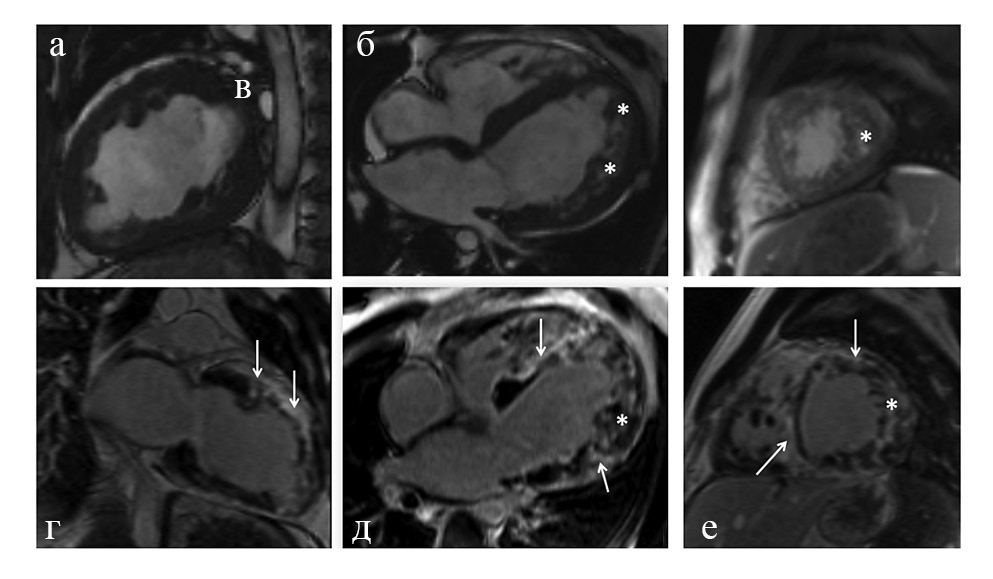

В качестве демонстрации случая ДТ приводим клинический пример пациентки 38 лет. По данным МРТ сердца с гадолинием (рис. 4) отмечается двухслойное строение миокарда ЛЖ в области нижних, передних, переднебоковых, нижнебоковых сегментов, соответствующее критериям некомпактной кардиомиопатии (более чем в 6 сегментах).

Рис. 4, а–б – МРТ сердца в кино-режиме, SSFP-последовательность: а – длинная ось, четрырехкамерная проекция; б – короткая ось; *слой НМ толщиной до 18 мм; в–г – отсроченное контрастирование, IR-последовательность с подавлением сигнала от миокарда. Стрелки указывают на протяженные участки субэпикардиального контрастирования (некоронарогенной природы) в перегородочных и переднебоковых сегментах.

Толщина компактного слоя в этих сегментах составляет 1,8–3,4 мм, некомпактного – 10–17 мм. Некомпактный слой представлен губчатым миокардом. Индексированная масса НМ составляет 41 г/м2 (при норме до 15 г/м2), что составляет 37,7% от массы миокарда ЛЖ (при норме до 25%), ФВ 31%.